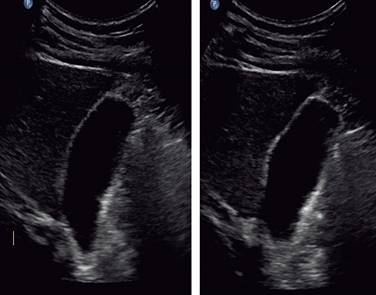

A un mes de su egreso, se presenta en consulta sin presentar cuadro de dolor abdominal o cambios que afecten su calidad de vida, realizando sus actividades de la vida diaria. Se cita nuevamente a siete meses de su alta con USG de hígado y vías biliares de control en el que no se observan datos de proceso inflamatorio agudo en vesícula biliar (Figura 6), asimismo clínicamente se refiere asintomático, se decide alta del servicio.

Figura 6: Imagen de ultrasonido en la que se observa vesícula biliar sin contenido hemático, de paredes delgadas, sin solución de la continuidad ni líquido libre perivesicular.